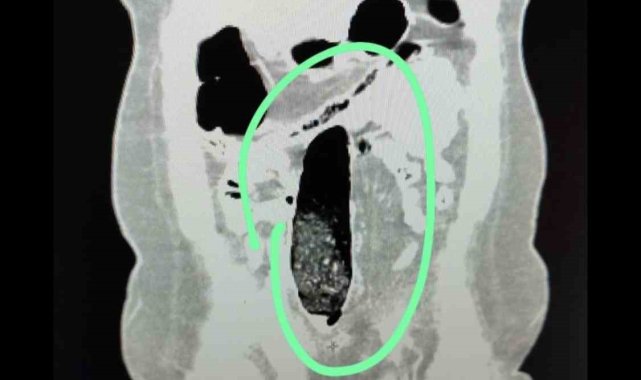

Muş İl Emniyet Müdürlüğü ekiplerince şehirler arası otobüste yakalanan 2 İran uyruklu şahsın vücutlarında uyuşturucu madde ele geçirildi.Muş İl Emniyet Müdürlüğü Narkotik Suçlarla Mücadele Şube Müdürlüğü ekiplerince, il genelinde uyuşturucu madde ticareti ve kullanımının önlenmesine yönelik yürütülen teknik ve analiz çalışmaları kapsamında, şehirler arası otobüslerle uyuşturucu sevkiyatı yapılacağı değerlendirildi. Bu değerlendirme üzerine durdurulan şehirler arası yolcu otobüsünde bulunan 2 İran uyruklu şahıs üzerinde yapılan kontrollerde şüpheli durum tespit edildi. Şahısların iç beden muayeneleri sonucunda, vücutlarının doğal boşluklarında ve bağırsaklarında uyuşturucu madde bulunduğu belirlendi.Tıbbi müdahale sonucu; F.V. isimli kadın şahıstan 3 parça halinde toplam 397,78 gram metamfetamin, S.İ. isimli erkek şahıstan ise 24 adet sentetik hap ile 3 parça halinde toplam 167,68 gram metamfetamin ele geçirildi.Şüpheliler hakkında TCK 188 Uyuşturucu veya Uyarıcı Madde İmal ve Ticareti suçu kapsamında adli işlem yapıldı. Adli mercilere sevk edilen şahıslar tutuklanarak cezaevine gönderildi.